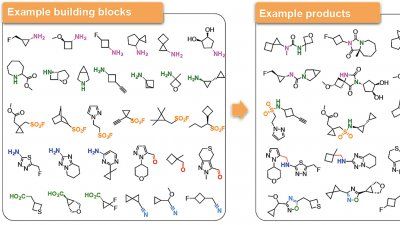

Scientists at UCSF, in collaboration with colleagues at UNC, have developed the world’s largest virtual pharmacology platform and shown it is capable of identifying extremely powerful new drugs.